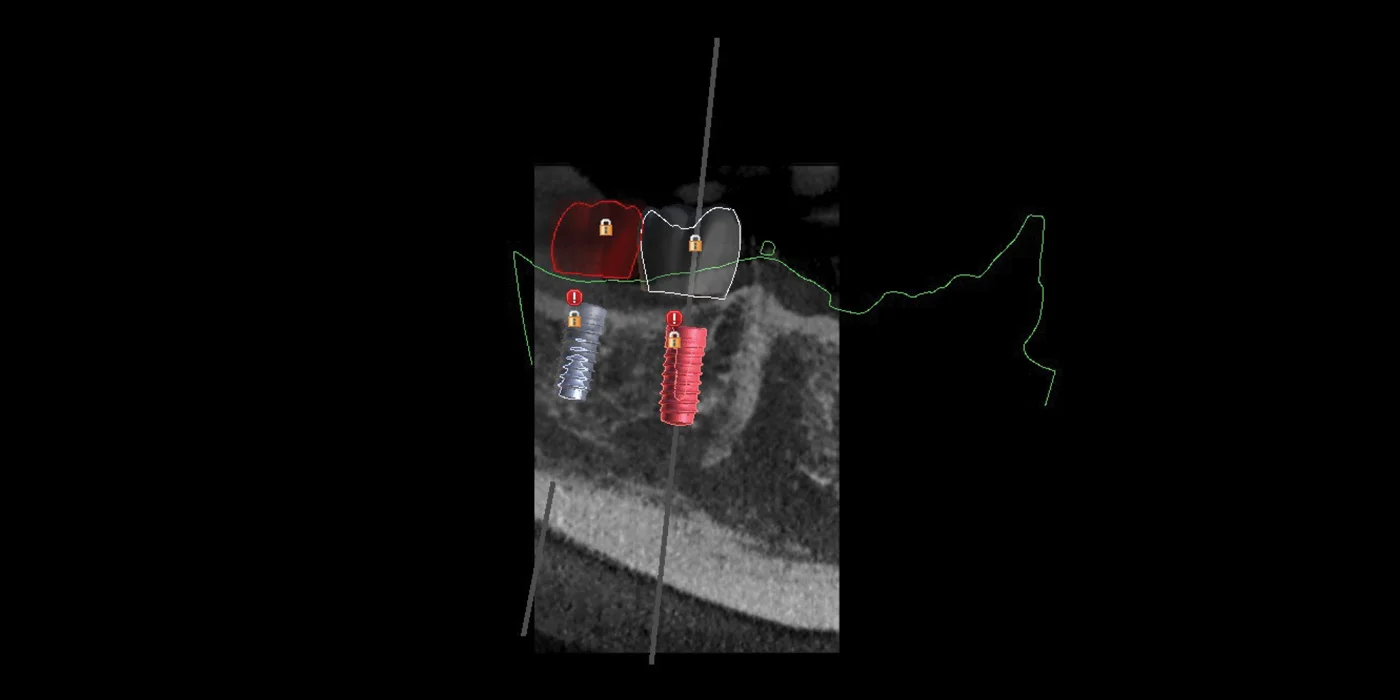

Implants and comprehensive prosthetic restorations

In implantology and implantoprosthetics special software enables e.g. creation of surgical templates. They precisely determine the location of the implanted implant. In orthodontics 3D digital intraoral scanning allows images to be fed into software that calculates various types of indicators. They are needed for precise orthodontic treatment planning by the doctor. We create virtual occlusal analyzes and simulations of treatment effects, including optional extractions and future tooth root alignment. The patient sees the final effect of the treatment on his face in the computer even before putting on the camera. There are also tools for digital monitoring of the progress of orthodontic treatment. Thanks to them, the patient has a chance to do documentation at home and anywhere in the world (so-called dental monitoring), staying online with the doctor using a special application.